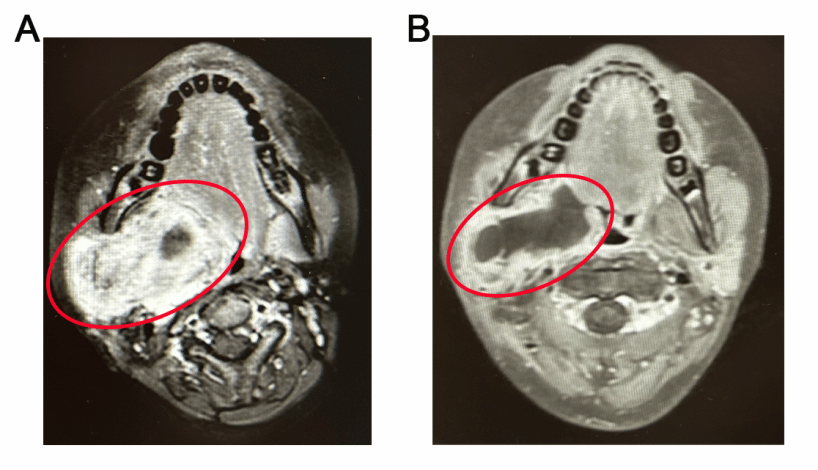

晶格放疗疗效对比:A.晶格放疗前 B.晶格放疗后 红色为肿瘤区域。

经过5次晶格放疗后,患者的复查结果显示:肿瘤体积显著缩小,边缘形成钙化带,中央区域出现坏死液化区。目前患者仅偶有轻微张口受限,生活质量大幅改善。